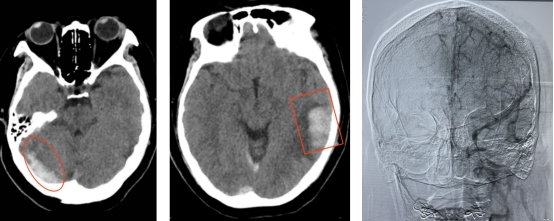

术前影像

静脉血栓影 静脉性脑出血 静脉窦广泛血栓